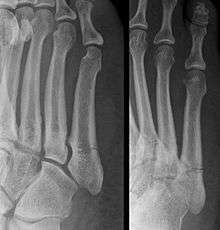

This injury should be differentiated from the developmental apophysis (5th metatarsal tuberosity) commonly and normally occurring at this site in adolescents. Differentiation is possible by characteristics such as absence of sclerosis of the fractured edges (in acute cases) and orientation of the lucent line: transverse (at 90 degrees) to the metatarsal axis for the fracture (due to avulsion pull by the peroneus brevis muscle inserting at the proximal tip) - and parallel to the metatarsal axis in the case of the apophysis. Diagnostic x-rays include anteroposterior, oblique, and lateral views and should be made with the foot in full flexion.

A legitimate concern in any fracture is whether the fracture will heal quickly and without complication. Failure of the fractured ends to unite is called non-union and its frequency varies with the fracture site, some fracture sites being notorious for non-union. An example of such would be a scaphoid (navicular) fracture of the wrist. Such a complication also involves fractures of the proximal end of the fifth metatarsal, such as the Jones fracture. This has been the subject of interest, and initially led to the description of three zones at the proximal end of the fifth metatarsal.

Zones I and II have been associated with relatively guaranteed union and this union has taken place with only limited restriction of activity combined with early immobilization. On the other hand, zone III has been associated with either delayed or non-union and, consequently, it has been generally agreed that fractures in this area should be considered for some form of internal immobilization, such as internal screw fixation. More recently, because of the similar behavior of the original zones I and II, it has been suggested that zones I and II be combined leading to current recommendations for two zones, zone I being associated with uncomplicated union, and zone II being prone to nonunion and therefore considered for internal fixation.

These zones can be identified anatomically and on x-ray adding to the clinical usefulness of this classification.[3] It should be emphasized that surgical intervention is not, by itself, a guarantee of cure and has its own complication rate. Other reviews of the literature have concluded that conservative, non-operative, treatment is an acceptable option for the non-athlete.[4]